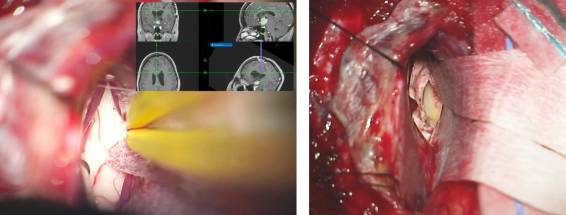

图2. 图示一例三脑室前部鞍上脊索样胶质瘤。该病例既往在其他医疗机构采用经额叶皮层入路手术。因为该手术入路的工作角度受限,最后不得不放弃全切。笔者在离断透明隔静脉后采用了经胼胝体-经扩大室间孔-经静脉入路最后分离并切除了前方脊索样组织。注意视交叉位于肿瘤下方(黄色箭头)和经终板的狭小空间。这些特点限制了经鼻和经额下手术入路。

图9. 神经导航是引导术者通过合理而有限的切开胼胝体(左图),从预期的手术角度到达到室间孔的关键所在。2cm的胼胝体切开恰好位于中线右侧,显露右侧脑室(右图)。在脑室汇聚点释放脑脊液进一步松弛额叶。注意用缝线牵引大脑镰上方适当推移上矢状窦。